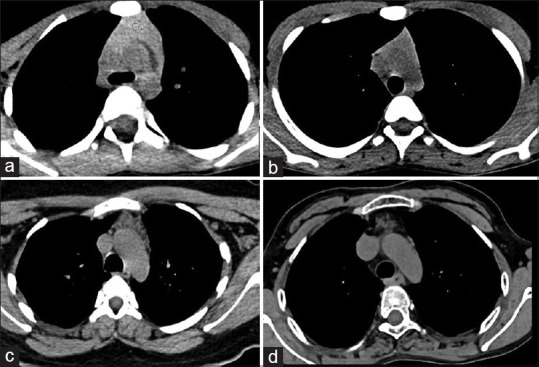

Background: Thymus is a T-cell-producing lymphoid organ that appears prominent in the paediatric population and involutes in size with ageing. The gland shows a wide variety of appearances across different age groups. The purpose of the study is to evaluate the computed tomography (CT) appearance of thymus gland in the normal population with a focus on size, CT attenuation and fatty infiltration in different age groups.

Patients and methods: This is a retrospective study done after taking approval from the Institutional Ethics Committee. Patients undergone CT scans of the thorax were identified from our database. All evaluations were done in non-contrast CT scans. Patients having underlying diseases that may have associated thymic abnormality were excluded. The appearance of thymus and the presence of fatty replacement were assessed. The size of thymus (length and thickness of right limb and left limb) and non-contrast CT Hounsfield unit (HU) value of thymic tissue were measured and compared in various age groups.

Results: Four hundred and fifty patients were included, 262 (58.2%) were male. Mean age was 33.6 ± 17.1 years, range (3 months-80 years). The size of thymus was observed to decrease with increasing age. The mean age of complete fatty replacement in our study was 45 years. Complete fatty replacement was noted in all cases with an age of more than 60 years. The most common shape was arrowhead, and the most common location was pre-aortic and para-aortic location. Non-contrast CT HU value was maximum in infants and gradually decreased with advancing age.

Conclusion: Even normal thymus can show varied appearance on CT which changes with the age of the patient being imaged. A comparison with normative data could help differentiate normal from abnormal glands to avoid unnecessary intervention.